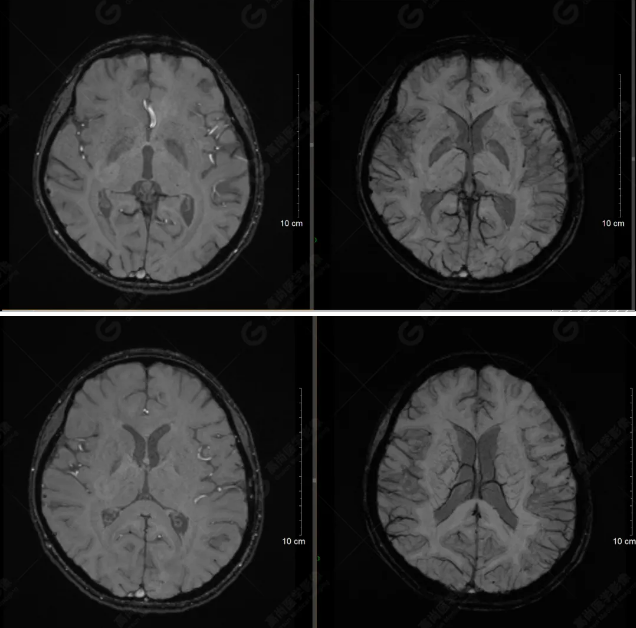

以下是T1WI軸位掃描及矢狀位掃描:

雙側(cè)大腦半球?qū)ΨQ,灰白質(zhì)對比正常,顱內(nèi)未見異常信號影。腦室系統(tǒng)未見擴(kuò)大,中線結(jié)構(gòu)居中。腦溝、裂未見增寬。幕下小腦、腦干未見異常。矢狀位示垂體形態(tài)、大小級信號未見異常。所示左側(cè)乳突內(nèi)見多發(fā)短T1長T2信號影。

顱腦MRI平掃未見明顯異常,左側(cè)乳突內(nèi)積血,建議補(bǔ)充SWI檢查。